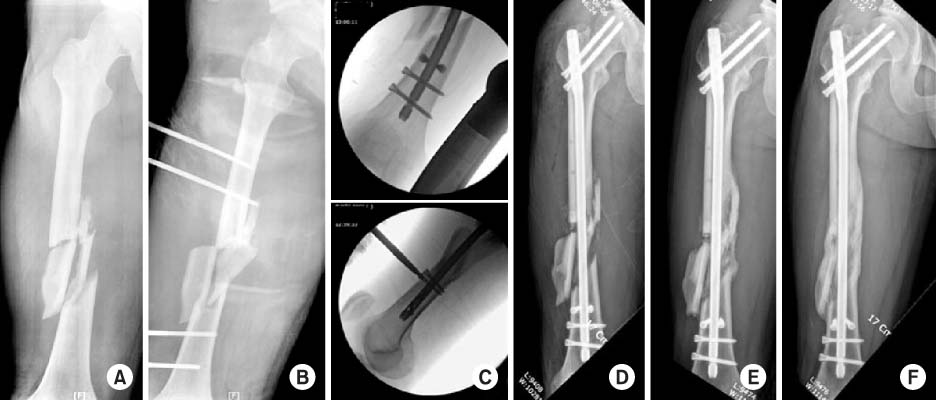

Fig. 1

(A) Three-dimensional-reconstructed computed tomography image shows a fragmented wedge fracture at the femur shaft infraisthmal area. (B) Intra-operative C-arm images show the sequence of Poller screw insertion. (C) Postoperative radiograph shows a well reduced femur with good positioned Poller screws.

Fig. 1 (A) Three-dimensional-reconstructed computed tomography image shows a fragmented wedge fracture at the femur shaft infraisthmal area. (B) Intra-operative C-arm images show the sequence of Poller screw insertion. (C) Postoperative radiograph shows a well reduced femur with good positioned Poller screws.